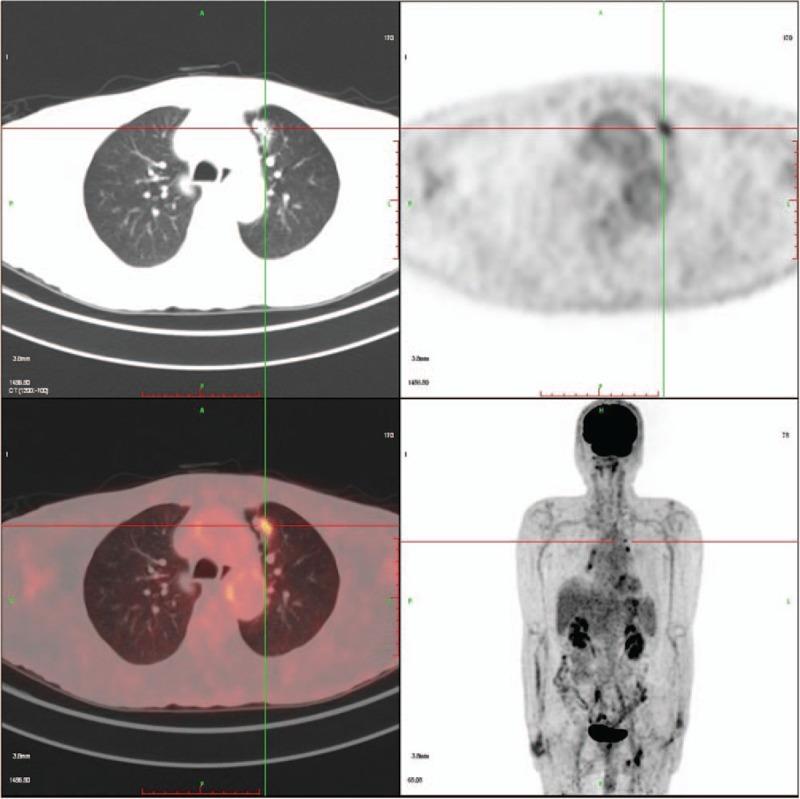

Here, we present a case of a man, heavy smoker who initially presented with stage IA lung adenocarcinoma (LADC). Three years after a lung lobectomy, he was diagnosed with advanced lung squamous cell carcinoma (SCC), according to laboratory, imaging, and pathological examinations.

The case initially had an early-stage LADC with an L858R epidermal growth factor receptor (EGFR) mutation. A subsequent advanced SCC bearing EGFR L858R/T790M mutations occurred 3 years after surgery.

The comprehensive therapy we utilized, including surgical resection for the early-stage lesion and GP chemotherapy and local radiotherapy as the first line therapy along with gefitinib maintenance treatment for the advanced metachronous second primary tumors (MST).

在此,我们报告一例男性病例,该患者为重度吸烟者,最初诊断为IA期肺腺癌(LADC)。肺叶切除术后三年,根据实验室、影像学和病理检查,他被诊断为晚期肺鳞状细胞癌(SCC)。

该病例最初为早期LADC,伴有L858R表皮生长因子受体(EGFR)突变。术后三年发生了随后的晚期SCC,伴有EGFR L858R/T790M突变。

我们采用的综合治疗方法,包括对早期病变进行手术切除,以及将GP化疗和局部放疗作为一线治疗,同时对晚期异时性第二原发性肿瘤(MST)进行吉非替尼维持治疗。